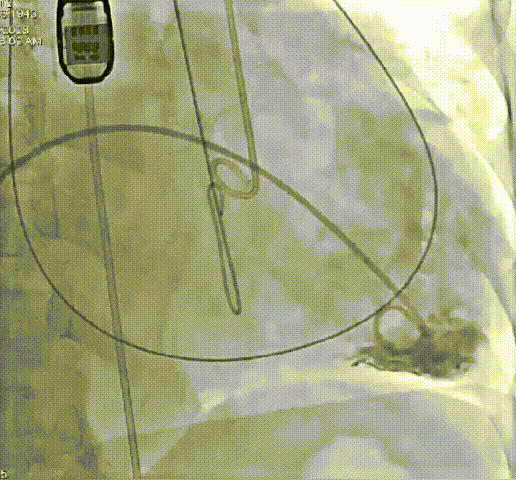

病例三

患者68岁,女性,“心房颤动”病史6年,近半年出现活动时气促。心脏超声:重度三尖瓣关闭不全,轻度二尖瓣关闭不全。“高血压”病史4年。TTVR术后三尖瓣关闭不全消失,无明显瓣周漏。

术前、术后造影结果